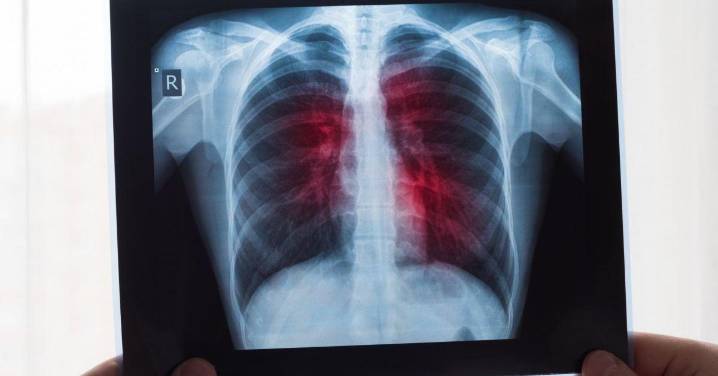

Un modelo de IA estima el riesgo de cáncer de los nódulos pulmonares La Region4 hrs agoFollow Share to:El estudio de los Países Bajos utilizó datos de amplios ensayos de cribadoSee Full Page112